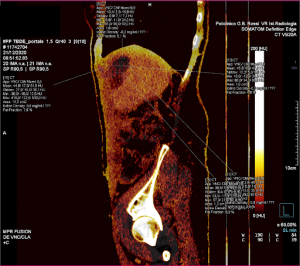

image

FIGURA 3. Analisi VNC in proiezione sagittale, in cui si evince la distanza cranio-caudale tra le ROI superiore, centrali e inferiore.